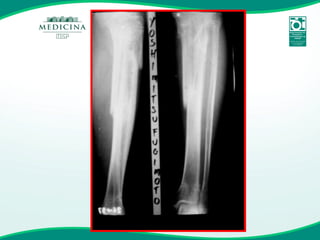

FRATURA  DOS OSSOS DA PERNA BILATERAL

YF 72a FUMANTE

FRATURA  DOS OSSOS DA PERNA